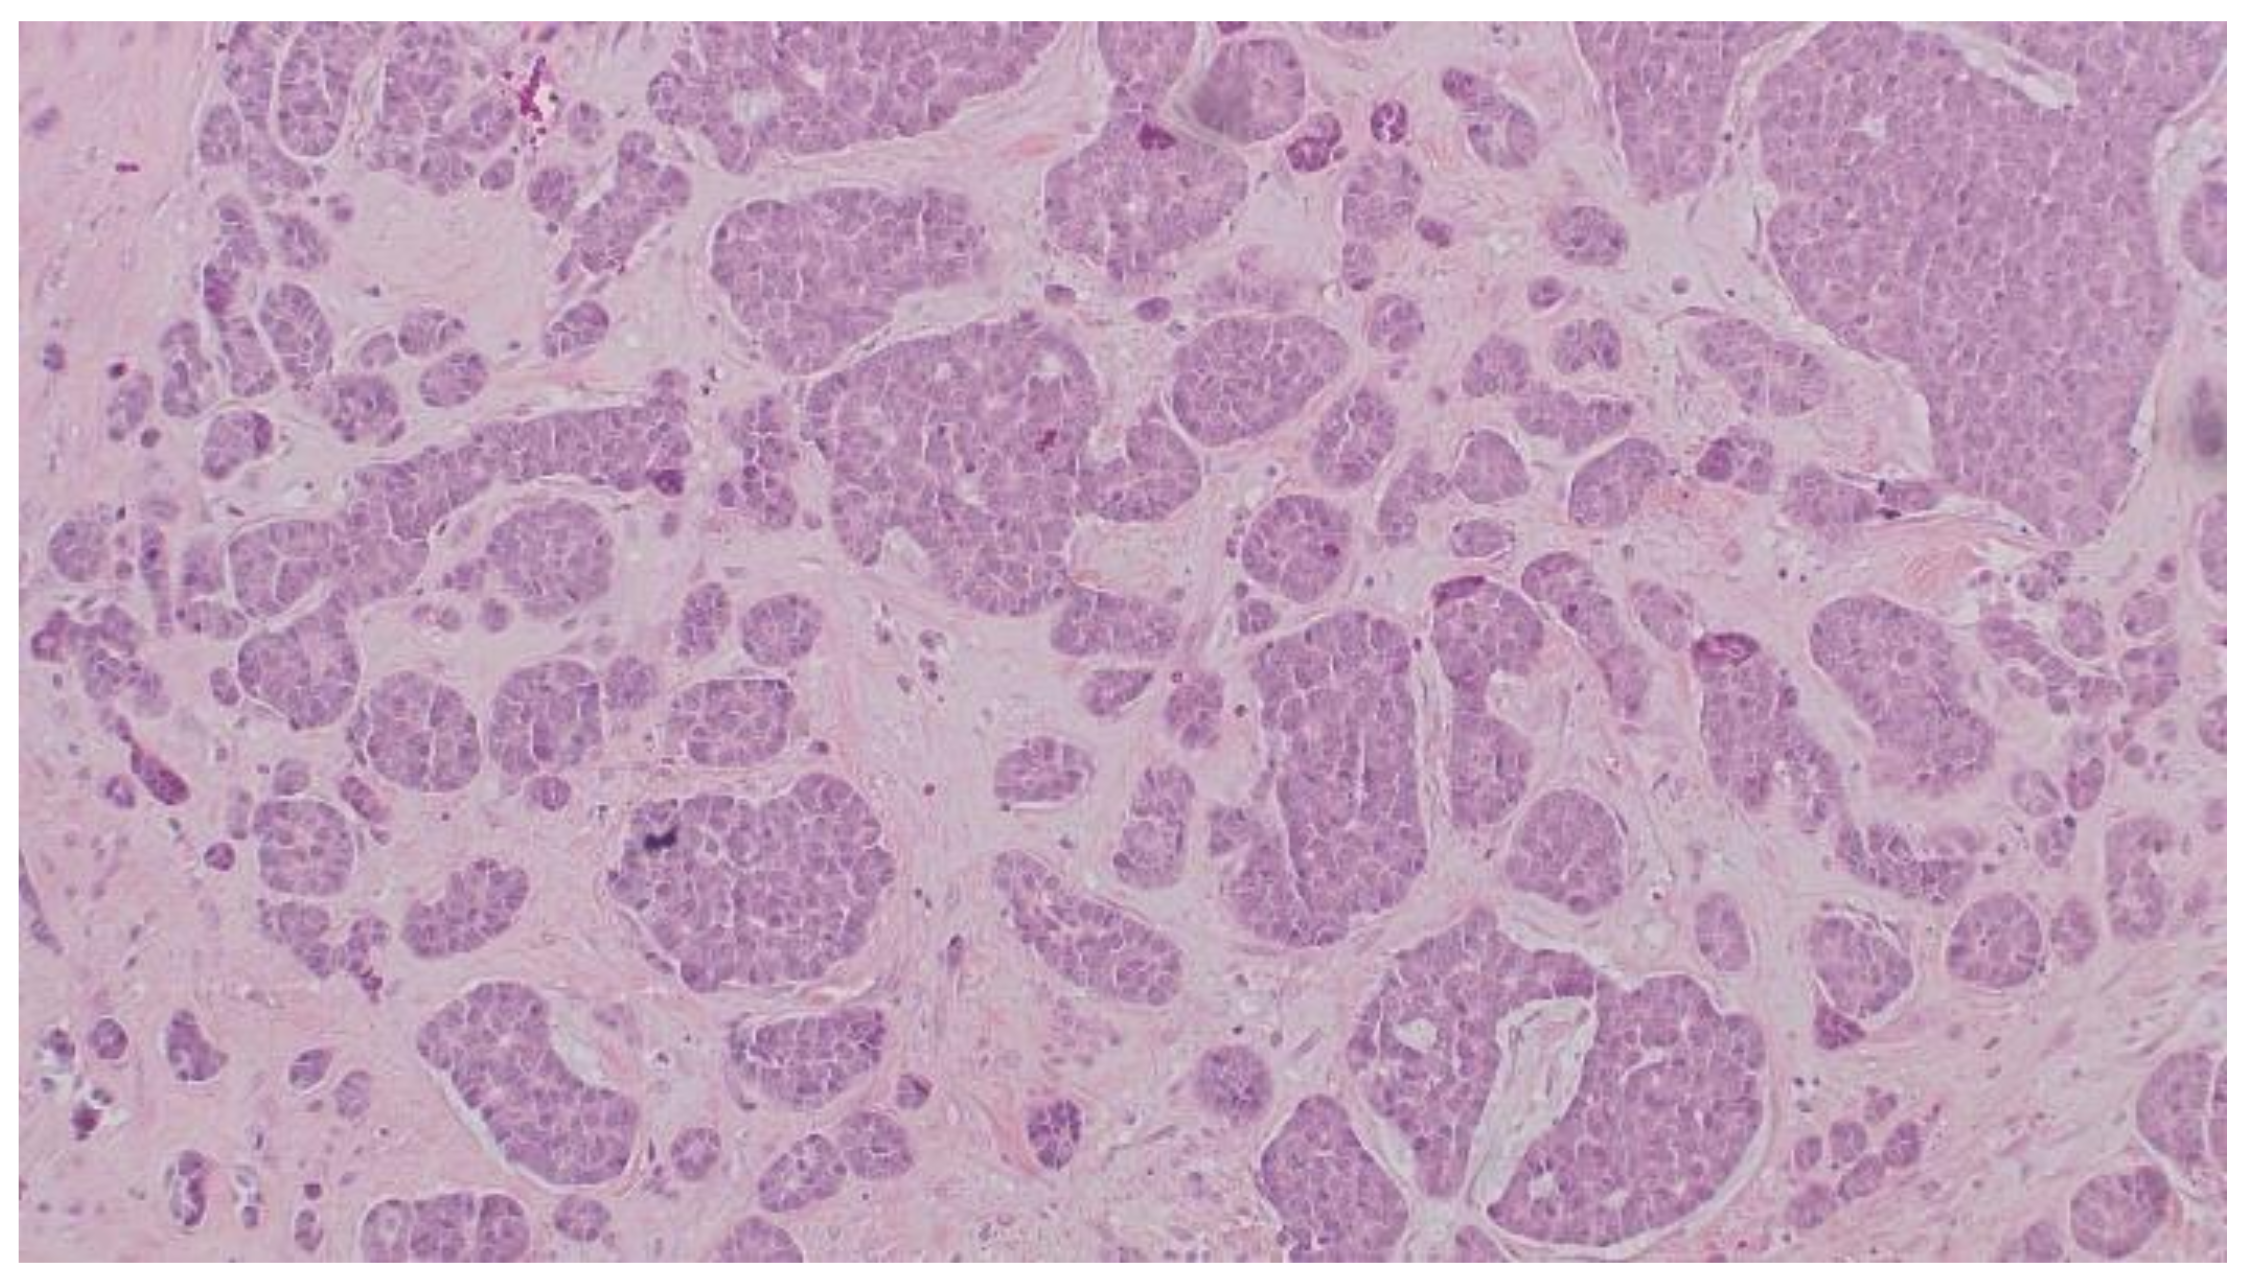

2. Case Report